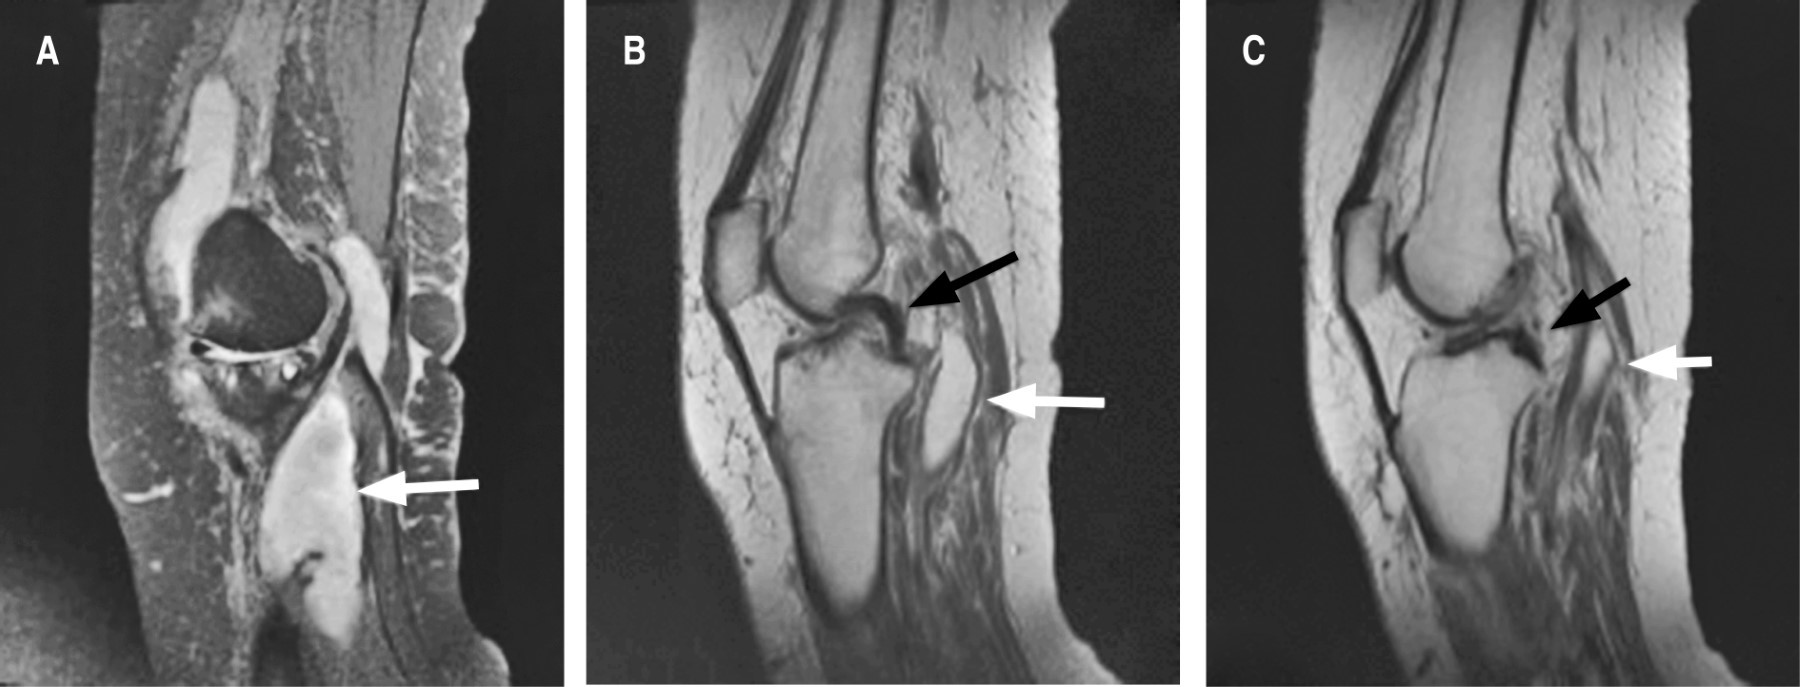

Se continuó abordaje diagnóstico con resonancia magnética de rodilla izquierda en la que se reportó: quiste de Baker, desgarro del ligamento cruzado anterior, derrame articular, contusión y acodamiento del ligamento cruzado posterior, desgarros meniscales complejos (Figura 3). En las imágenes obtenidas se visualizó un quiste de Baker de gran tamaño que no podía ser correctamente definido por las grandes dimensiones del mismo, así como por falta de cortes distales para observar bien el tamaño. Por tal motivo, se solicitó complemento de resonancia magnética de pierna izquierda simple y contrastada con proyecciones angiográficas: trayectos vasculares regulares en todos los segmentos explorados. Se observa desplazamiento de estructuras vasculares que no compromete el calibre ni morfología (Figura 4). Dicho desplazamiento se debe al efecto de masa que condiciona una lesión quística que corresponde a quiste de Baker que se extiende hasta tercio distal de la pierna, el cual presenta heterogeneidad intraluminal, con pliegues parciales de la sinovial que es de grosor uniforme y delgada, reportándose con medidas de 31 × 4.6 × 3.9 cm, con volumen de 289 cm3; posterior a la aplicación del gadolinio, no muestra reforzamiento que sugiera otra patología. Edema en tejido graso subcutáneo, identificando colecciones pequeñas adyacentes a fascias musculares de caras medial y lateral en tercios medio y proximal (Figura 5). Como complemento, se realizaron pruebas de laboratorio para descartar artritis reumatoide; se encuentra factor reumatoide y anticuerpos contra péptido cíclico citrulinado negativos; además, la paciente no cumplía con el resto de los criterios diagnósticos para artritis reumatoide. El tratamiento inicial para la paciente fue manejo conservador con antiinflamatorios no esteroideos e inicio de fisioterapia. Se propuso manejo quirúrgico, así como punción y drenaje del quiste, pero, al contar con los antecedentes cardiovasculares ya mencionados, la paciente rechazó este manejo y se continuó con un tratamiento conservador a base de antiinflamatorios, fisioterapia y vigilancia. A los seis meses de seguimiento, la paciente presenta mejoría clínica y funcional basada en la exploración física y en la sintomatología. Se solicitan estudios de imagen de control, los cuales rechaza la paciente por motivos personales; se decide continuar con seguimiento en la consulta externa con base en clínica y funcionalidad.

Figura 3